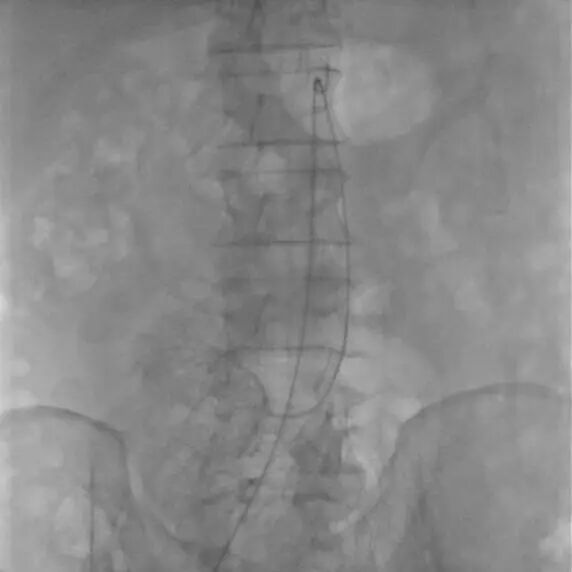

治疗通路建立

患者取仰卧位,双侧腹股沟区消毒铺单后局麻下分别经双侧股动脉穿刺置入7F(右侧)/5F(左侧)血管鞘组,予40mg肝素钠静脉注射全身肝素化,先经左股动脉插入4FRH导管,将导管头端置于肠系膜上动脉开口处,注入对比剂行肠系膜上动脉IADSA;再经右侧股动脉插入7F长鞘至肠系膜上动脉开口,旁路加压滴注生理盐水;明确病情后选取工作角度,先经4FRH导管路途下同轴送入1.7F栓塞微导管,旁路加压滴注生理盐水,经微导丝配合将其头端至于肠系膜上动脉夹层囊状动脉瘤腔内,于动脉瘤填入5枚弹簧圈行夹层动脉瘤弹簧圈填塞术;经右侧股动脉长鞘入路沿导丝送入1枚支架(SmartFlex 6mm×80mm,USA)该支架具有可预见的近端定位+参考Marker,准确定位后行肠系膜上动脉真腔成形术,支架覆盖夹层段。复行肠系膜上动脉IADSA示:支架位于肠系膜上动脉主干夹层段,支架覆盖夹层动脉瘤出入破口,支架内血流通畅,分支血管显影良好,支架以远血管主干及分支显影较术前增多增浓,多发夹层动脉瘤腔内弹簧圈均匀填塞。手术结束,使用Exoseal封堵止血系统闭合双侧股动脉穿刺点。